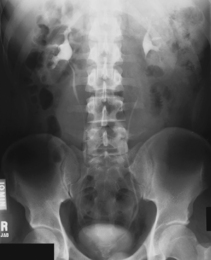

• Supine, midsagittal plane aligned and centered to centerline, support placed under knees, no rotation

• Erect, midsagittal plane aligned and centered to centerline, no rotation

• Center IR to iliac crest—ensure that bladder area, including the symphysis pubis, is included at lower IR margin.